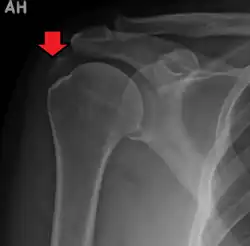

| A plain X ray of the shoulder showing calcific tendinitis | |

Calcific tendinitis is typically diagnosed by physical examination and X-ray imaging.[1] During the formative phase, X-ray images typically reveal calcium deposits with uniform density and a clear margin.[1] In the more painful resorptive phase, deposits instead appear cloudy and with unclear margins.[1] By arthroscopy, formative stage deposits appear crystalline and chalk-like, while resorptive stage deposits appear smooth resembling toothpaste.[1] Ultrasound is also used to locate and assess calcium deposits. In the formative stage, deposits are hyperechoic and arc-shaped; in the resorptive stage deposits are less echogenic and appear fragmented.[1][3]